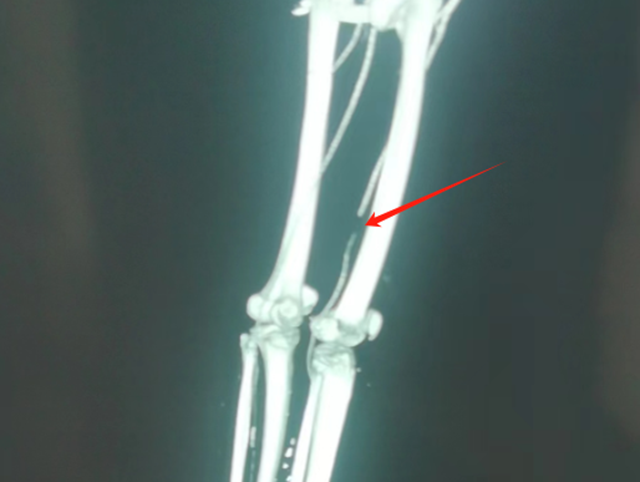

“该患者能保住性命,多亏了那根侧支血管(膝降动脉)。”贺智榆回忆说。

原来,刘大叔从山上滚下来的过程中,树枝从正面戳入左大腿,不偏不倚地戳穿了左腿前侧,把侧面一根股动脉戳断了,这概率非常小。不幸中的万幸是在断掉的这根股动脉血管侧支,有一根异常发育的血管,比常人更粗大,发育得很好,且断掉的地方低于分支处。如果断的地方再高3-4厘米,即使是有这根侧支血管也无济于事。

正是因为这根侧支的粗大血管,延缓了病情进一步恶化,这才保住了刘大叔的性命,不然下肢的缺血坏死只是时间问题。